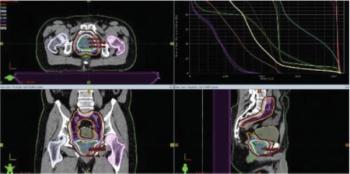

This case looks at an otherwise healthy 59-year-old man who was recently diagnosed with clinical stage IVB prostate adenocarcinoma. What is the most appropriate management for this patient?